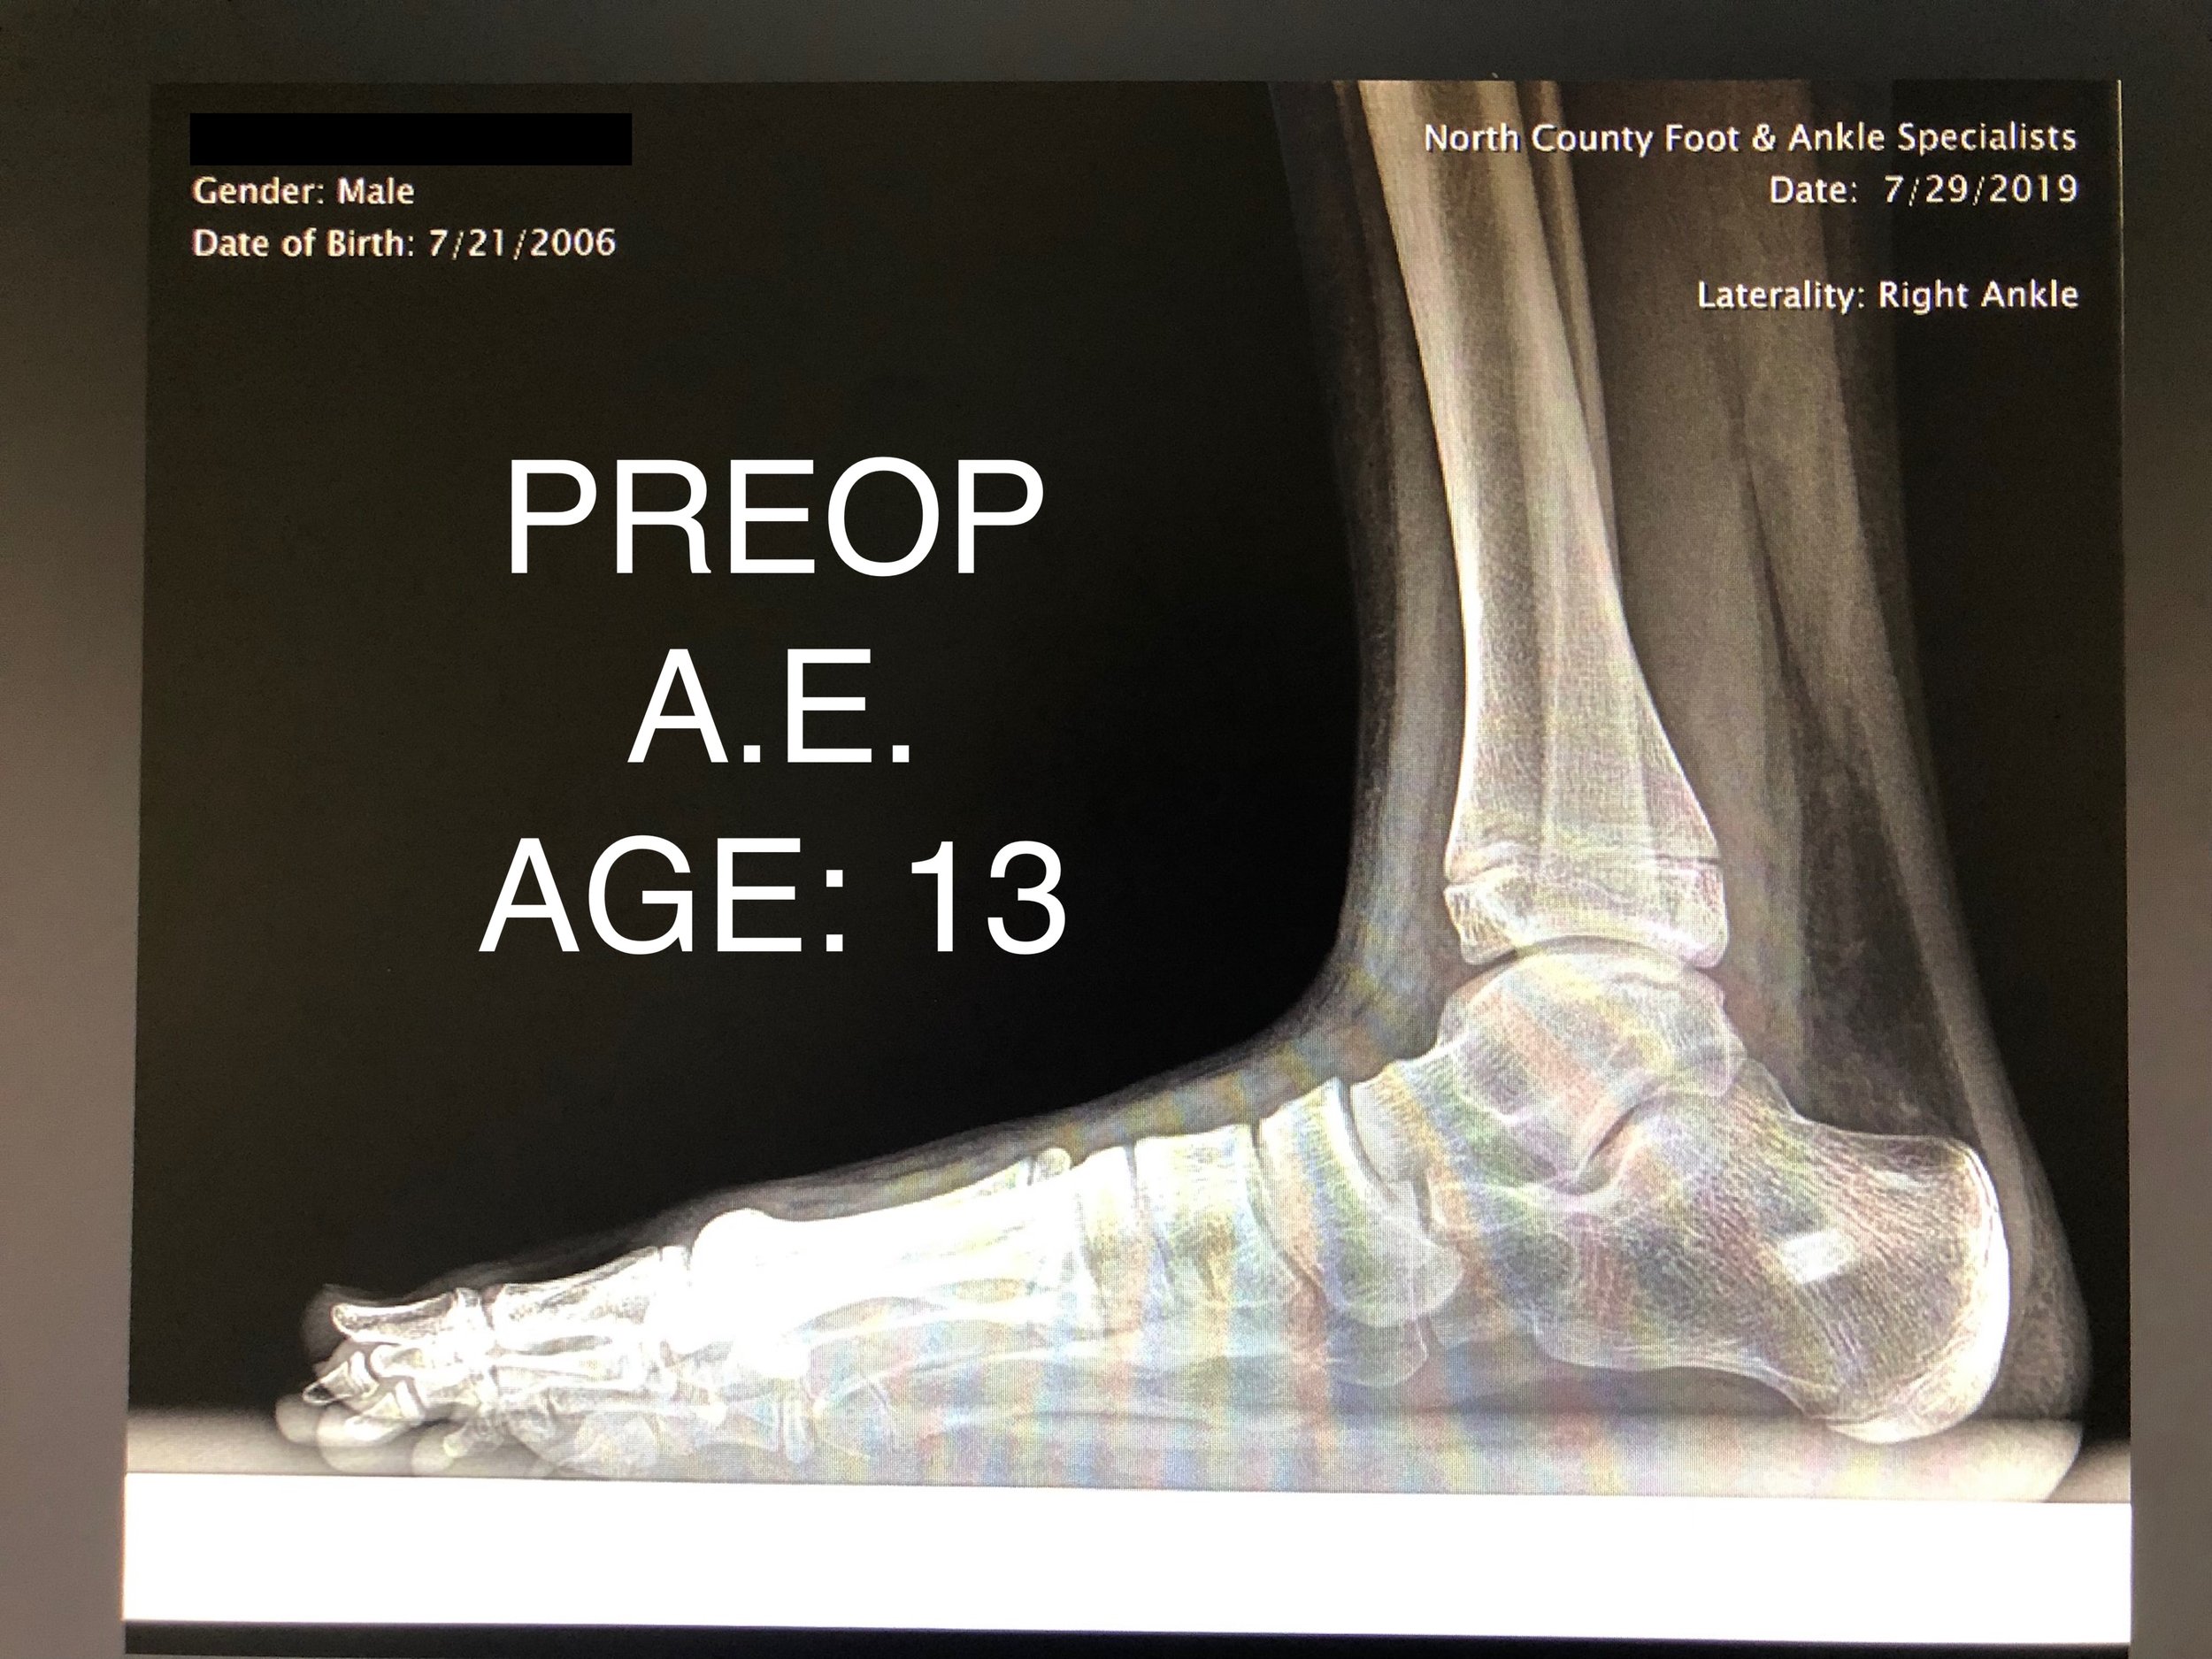

PEDIATRIC FLAT FOOT